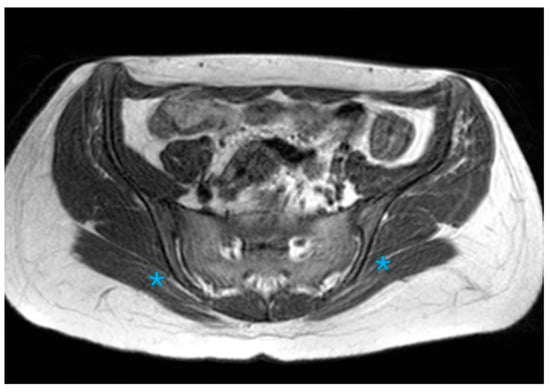

Assessment of Anatomical Variations in the Sacroiliac Joint Using Magnetic Resonance Imaging: A Retrospective Study of 840 Patients

Background/Objectives: This study aimed to examine the prevalence of anatomical variations in the sacroiliac joints (SIJs) as observed through Magnetic Resonance Imaging (MRI), to characterize their manifestations, and to identify MRI features that may resemble inflammatory alterations. Methods: A retrospective review was conducted on consecutive MRI scans of the SIJ performed from January 2009 to January 2022. Eight anatomical variations, along with associated edematous and structural changes, were assessed. Results: The study encompassed 840 patients, with anatomical variations identified in 39.7% of the cohort, occurring more frequently among female participants. The most prevalent variations were accessory SIJ (36.2%) and the iliosacral complex (32.2%). Notably, isolated synostosis and persistent ossification center variations were absent. The increased frequency of variations in women, as well as their correlation with advancing age, was statistically significant (p = 0.034). Accessory SIJ and dysmorphic alterations were linked to bone marrow edema and structural modifications. In the iliosacral complex and semicircular defect variations, prominent vascular structures were observed extending along the bone surfaces. The number and depth of edema slices in sacroiliitis exceeded those observed in the variation (p < 0.001). Conclusions: Anatomical variations of the SIJ are prevalent among women and tend to increase with advancing age. Given that these variations, particularly accessory SIJ and dysmorphic alterations, may present with edematous and structural signal intensity changes that resemble sacroiliitis, it is crucial to recognize these variations. It is recommended to assess axial and coronal images concurrently and to exercise caution in the interpretation of SIJ MR images. Full article

Show Figures

Figure 1